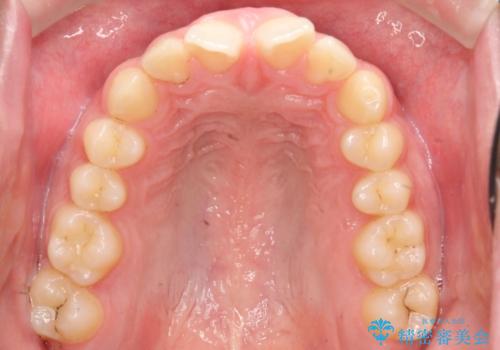

初診時の歯並びの状態としては、上下ともに前歯部の中等度のがたつきがあり、前歯には正中離開があり過蓋咬合を呈してい状態でした。

また奥歯の噛み合わせのズレもあり、特に左は顕著に認められました。